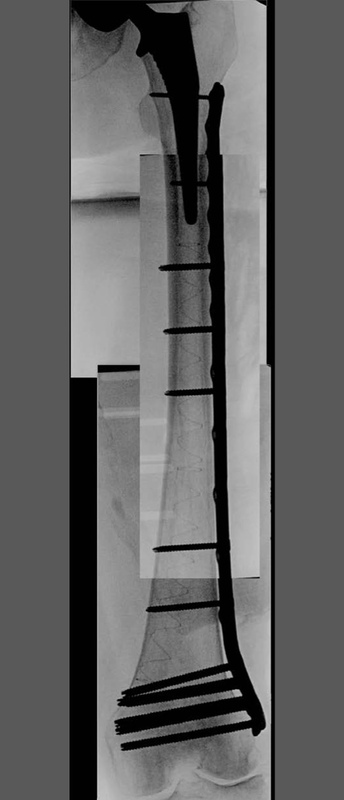

A 90-year-old patient presented with a periprosthetic femur fracture after a fall from a standing height fall. Patient is a community ambulator with no assistive walking device. X-rays revealed a long stem hip implant from a previous hemiarthroplasty. The fracture necessitated fixation and was treated operatively through a small incision in the medial distal femur. The guide wire was inserted to the tip of the stem before the implant was inserted. The IlluminOss implant was inserted, filled with liquid monomer, and cured with visible light. A plate and screw construct was placed laterally with screws extending into the hardened IlluminOss implant for support. Patient was allowed to weight bear as tolerated and reported no issues at follow up visit.